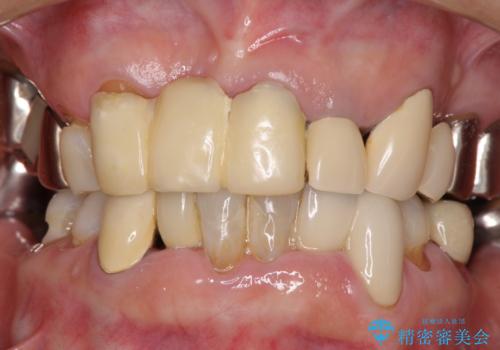

着色が著しい前歯のブリッジをオールセラミックできれいに

- 保険診療の前歯のブリッジが、形態も色も不自然で気になるとのことで来院された患者様です。

神経の抜かれている土台の歯は根管治療を行った上で、オールセラミックブリッジにより補綴することとしました。